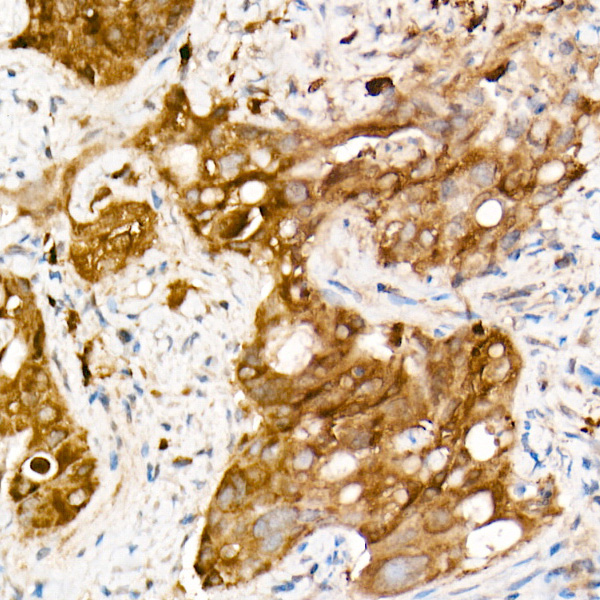

| Applications | ELISA, IHC-P |

The protein encoded by this gene binds copper and zinc ions and is one of two isozymes responsible for destroying free superoxide radicals in the body. The encoded isozyme is a soluble cytoplasmic protein, acting as a homodimer to convert naturally-occuring but harmful superoxide radicals to molecular oxygen and hydrogen peroxide. The other isozyme is a mitochondrial protein. In addition, this protein contains an antimicrobial peptide that displays antibacterial, antifungal, and anti-MRSA activity against E. coli, E. faecalis, S. aureus, S. aureus MRSA LPV+, S. agalactiae, and yeast C. krusei. Mutations in this gene have been implicated as causes of familial amyotrophic lateral sclerosis. Rare transcript variants have been reported for this gene.